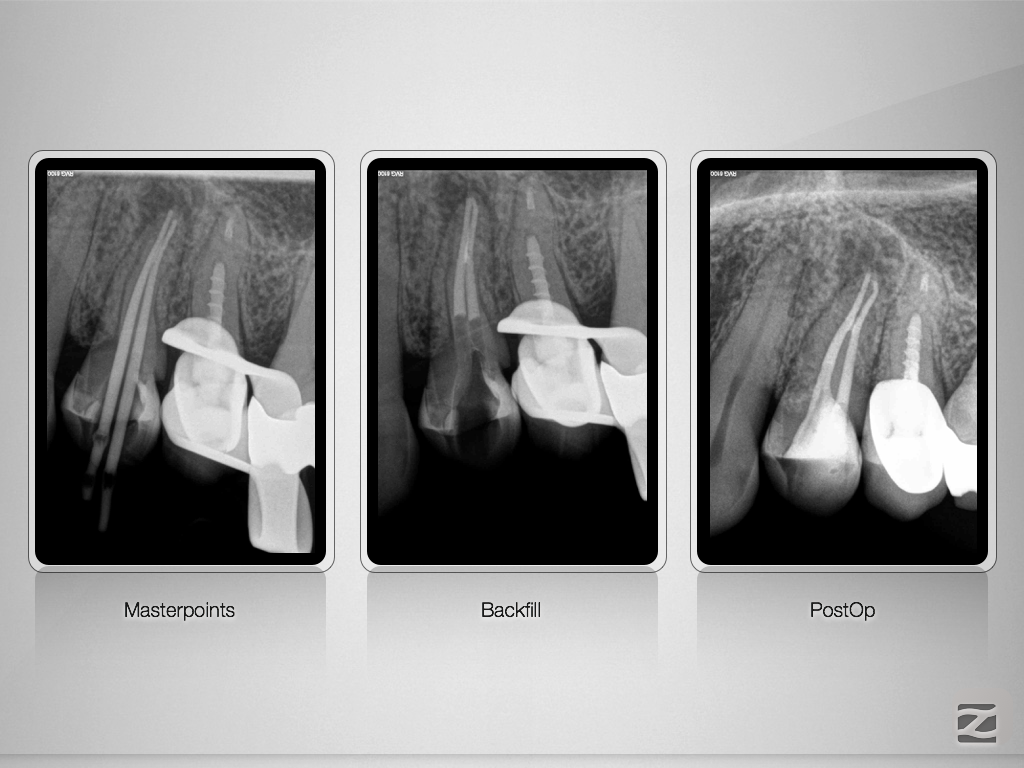

24D.005

Gib mir ein „H“